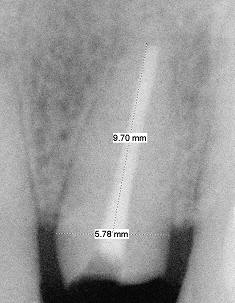

Fig.1 (higher magnification) Equigingival fracture. Root width at the crest is 6.78 mm, whereas height 9.70 mm. Return to main text